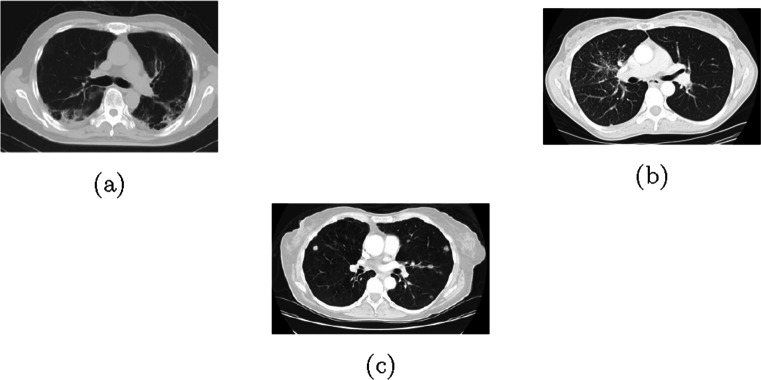

One of the promising methods to detect COVID-19 quickly and early in symptomatic people is by performing chest CT scans or taking chest x-ray images of patients [5]. To illustrate the difference between the COVID-19 positive CT scan and COVID-19 negative CT scan, COVID-19 negative CT scan images and COVID-19 positive CT scan images are shown in Figs. 5 and 6 respectively. CT has demonstrated high sensitivity in the detection of COVID-19 during the initial screening of the patient [6, 7]. It can be useful in rectifying false negatives obtained with rRT-PCR in symptomatic cases [8]. However, this is also a time-consuming process as an expert is needed to read these CT scans and x-ray images to determine if a person is COVID-19 positive.

Fig. 5.

COVID-19 Negative CT scan images

Fig. 6.

COVID-19 Positive CT scan images

- COVID-CT Dataset [44]: This dataset contains 349 COVID-19 CT images from 216 patients and 397 non-COVID-19 CT images. The positive images and negative images were collected from preprints related to COVID-19. Sample COVID-19 negative images are shown in Fig. 5 and sample COVID-19 positive images are shown in Fig. 6. Test and validation sets were collected from the hospitals.